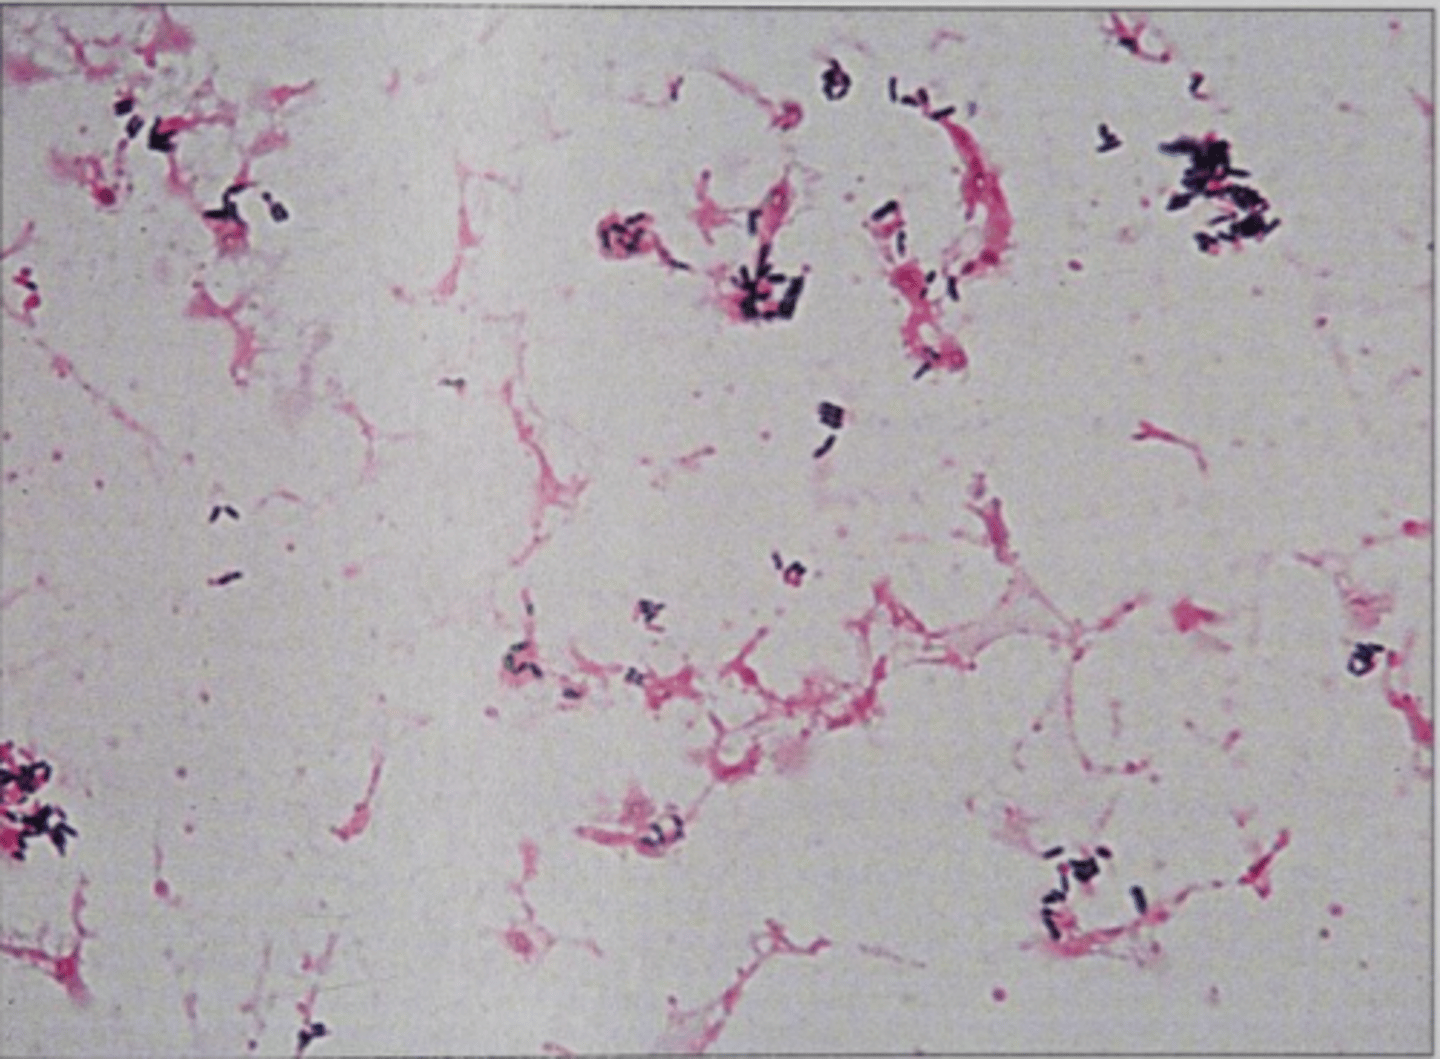

Actinomyces